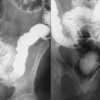

BADANIA KONTRASTOWE

Wykonywane jest przy użyciu specjalnych środków kontrastujących tzw. barytu, który pochłania promieniowanie rentgenowskie i dzięki temu uwidacznia patologie w badanym układzie, pozwala to uzyskać lepsze wyniki badań.

W przewodzie pokarmowym możemy zobaczyć np. zmiany zapalne, pourazowe, ciała obce, anomalie rozwojowe i inne.

Substancje kontrastujące spełniają pewne kryteria: są nieszkodliwe dla zdrowia zwierząt , nie biorą udziału w przemianach metabolicznych organizmu, gromadzą się wybiórczo w danym narządzie, są usuwane z organizmu drogami naturalnymi w jak najkrótszym czasie.